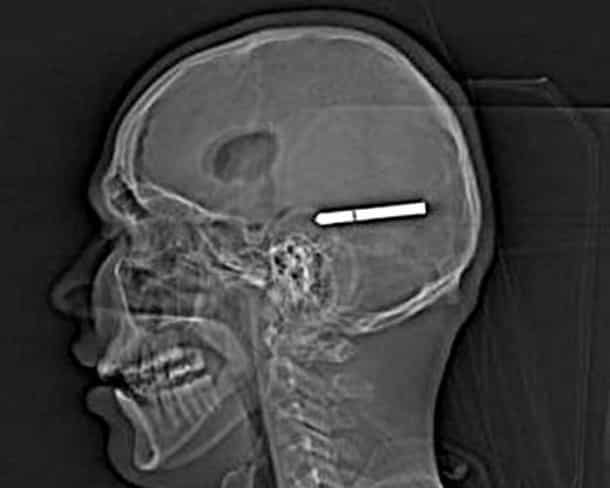

33 radiographies qui prouvent que les gens font des choses douteuses avec leur corps !